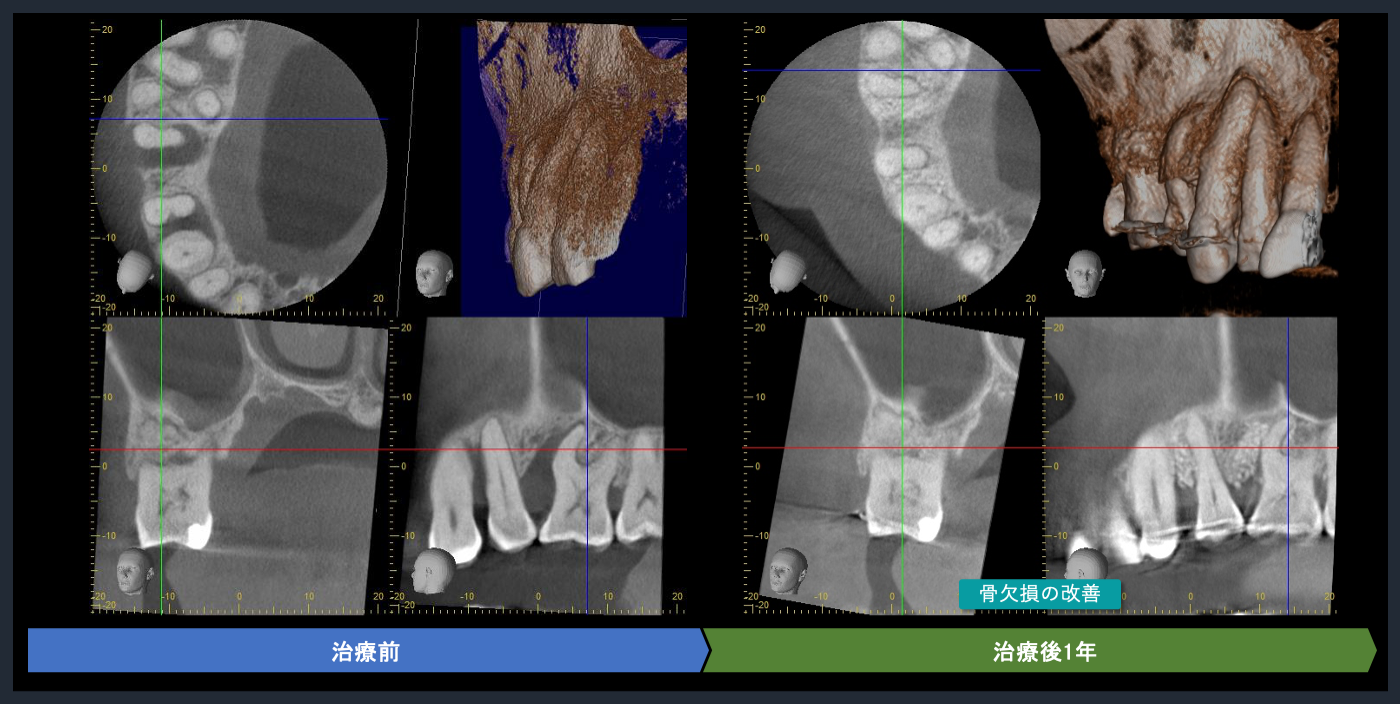

| 概要 | 歯周病が進行しており、右上臼歯部に重度の骨吸収像が認められます。失われた骨を再生し、歯の生存率を高めることを目的に、再生療法を試みました。良好な結果を得ることができました。問題なく使っていただいております。 再生療法を行う利点としては、ポケットが浅くなるので、患者様ご自身でのブラッシングで管理し、コントロールすることが可能になります。もちろん定期的なメインテナンスは必要不可欠です。 |

CTでの術前診査1

歯周基本治療後の再評価

Post-treatment evaluation

Post-treatment evaluation

CTでの術前診査2